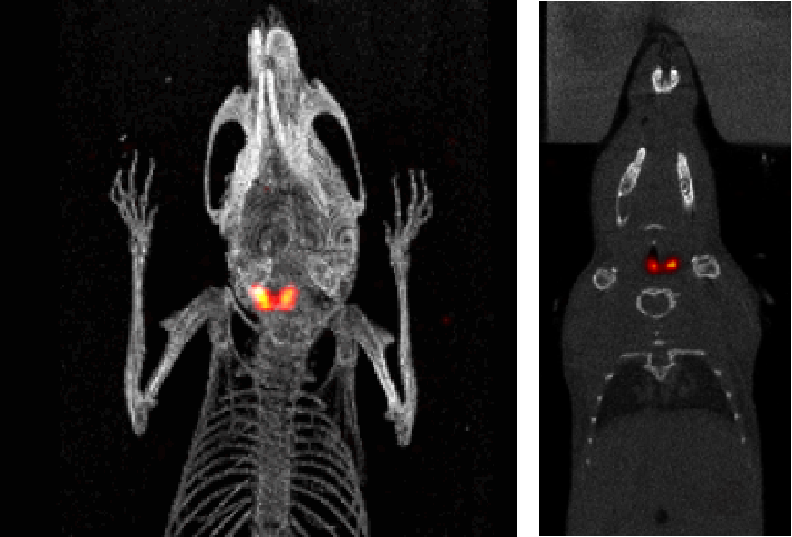

3、骨骼SPECT成像

SPECT/CT組合圖像,小鼠的骨骼成像:99mTc-HDP,94.35MBq (2.55mCi) @ start acquisition,采集時(shí)間60min。

骨骼成像.png

SPECT/CT組合圖像,大鼠的骨骼成像:99mTc-HDP,200MBq,采集時(shí)間45min。